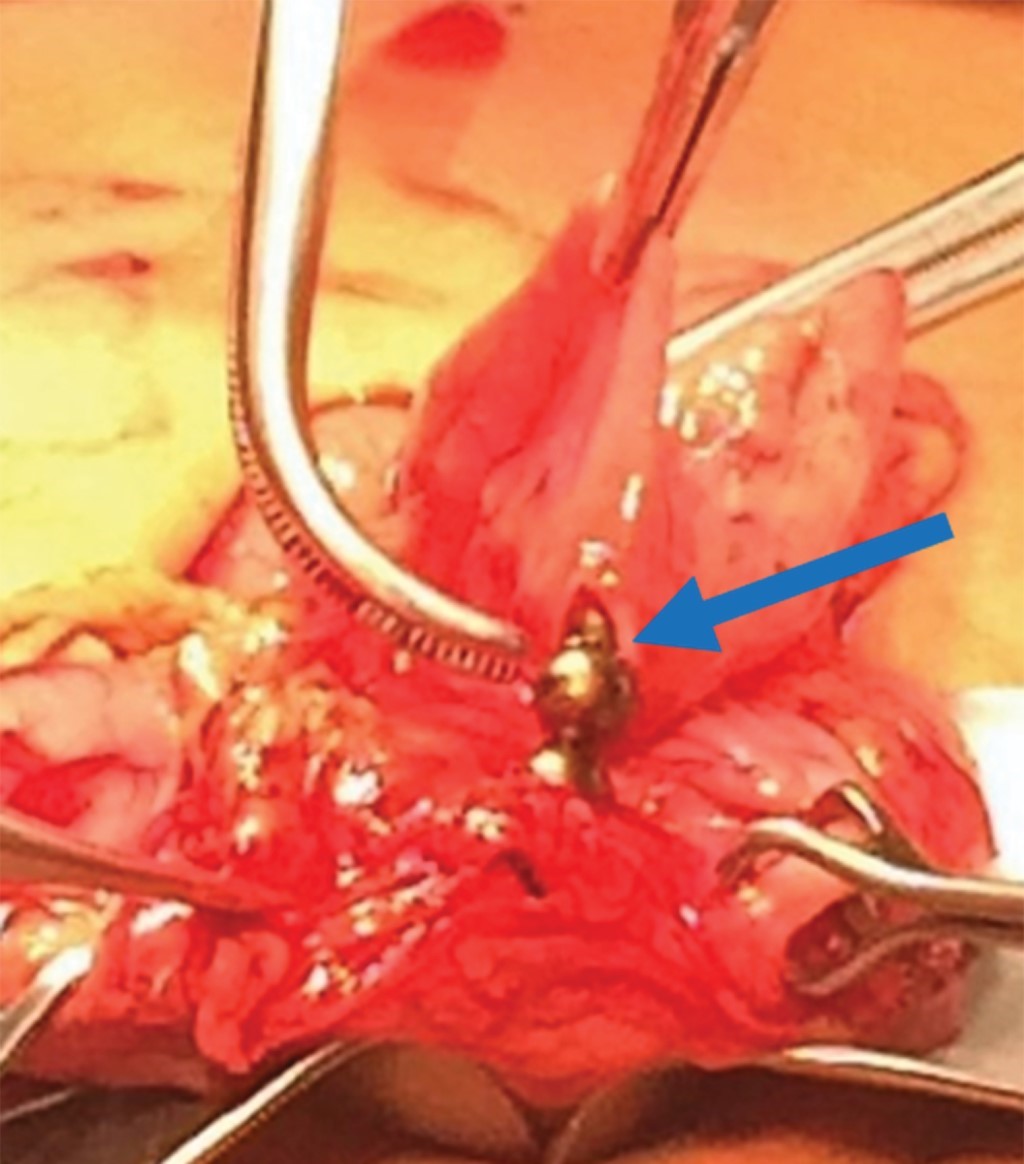

Se toma nueva radiografía de abdomen observando seis imanes más (Figura 5). Por sospecha de perforación, se realiza laparotomía exploradora encontrando que el epiplón cubre al estómago y al retirarlo se observa asa de intestino delgado pegada a la curvatura mayor del estómago. Al despegar el asa se aprecia un orificio en el intestino (localizado a 30 cm de la válvula ileocecal), el cual comunica con otro en el estómago. En esta porción intestinal se observan los seis imanes restantes (Figura 6). Se realiza resección de 6 cm de íleon con anastomosis término-terminal y en estómago se reavivan los bordes cerrando en dos planos. Se maneja con ayuno por cinco días, sonda nasogástrica, triple esquema antibiótico, omeprazol y analgésicos. La evolución es satisfactoria y se egresa a los siete días. Se le da seguimiento por seis meses permaneciendo asintomática.

Figura 6